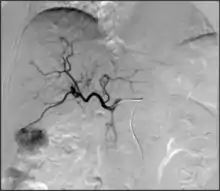

- Angiography: Imaging the blood vessels to look for abnormalities with the use of various contrast media, including iodinated contrast, gadolinium based agents, and CO2 gas.[3]

- Angiography: Sometimes referred to as traditional angiography, catheter angiography or digital subtraction angiography (DSA.) A small needle is inserted into a blood vessel, then exchanged for a catheter over a wire. The catheter is directed at the vessel to be studied, and contrast is directly injected to evaluate the lumen under video X-ray. This is an older technique than modern CT angiography or MR angiography, but provides unique advantages. With a catheter in place, provocative maneuvers can be performed such as breath holds or instillation of vasodilators, to evaluate a patient's blood flow dynamically. This can reproduce symptoms and identify functional abnormalities in a vessel that a static CT or MR imaging cannot.[79][80] Angiography provides the basis for all endovascular therapy.